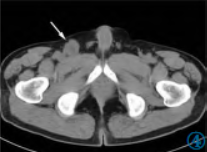

2 年前患者因发现右侧腹股沟区包块12 天再次入院。查体右侧腹股沟区可见触及肿物大小约3 cm×2 cm,质韧,边界尚清楚,活动度较差。腹部CT 增强(图4~6)示右侧腹股沟区可见类圆形软组织结节,大小约2.8 cm×2.3 cm,边缘尚清楚,平扫CT 值约31 HU,增强扫描静脉期CT 值约40 HU,肿物强化不明显,中央呈相对低密度。行超声引导下穿刺活检术,病理诊断为胃肠间质瘤(Gastrointestinal stromal tumor,GIST)。

图4~6 腹部CT 平扫轴位、静脉期轴位及矢状位图像示右侧腹股沟区类圆形软组织结节。